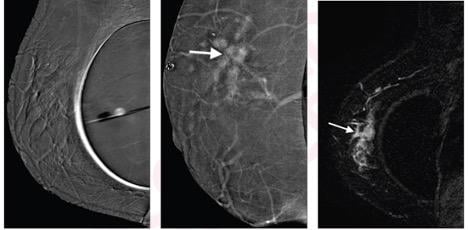

Left to right: Subtraction right mediolateral oblique (MLO) CEM was non-diagnostic because of artifact, potentially due to motion misregistration from extended exposure time; subtraction right MLO implant displaced CEM image shows 5.8 cm enhancing mass (arrow); contrast-enhanced MRI sagittal subtraction image shows concordant mass (arrow).

Noting that CEM has not been investigated in women with breast augmentation, Molly Carnahan and her Mayo Clinic team in Phoenix, AZ, concluded, “the findings suggest a possible role of CEM for staging in women with breast augmentation and contraindication or limited access to MRI.”

The index cancer histology was invasive ductal carcinoma (IDC) in 15 (88%) women, invasive lobular carcinoma (ILC) in 1 (6%), and ductal carcinoma in situ in 1 (6%). Median index cancer size was 2 cm, and 2 (12%) index cancers were mammographically occult. Ultimately, CEM and MRI were concordant for the index cancer in all 17 women.

Six additional lesions were demonstrated by CEM and confirmed by MRI in 6 (35%) women: 3 multifocal, 1 multicentric, 2 contralateral. Two of these lesions revealed malignant histopathology: 1 IDC, 1 ILC.

“MRI did not identify any additional cancers not identified on CEM,” the authors of this AJR article added.